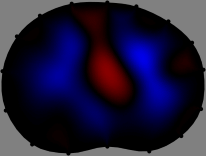

Refer to caption

Figure 1: Time-difference electrical impedance tomography. (Top) 16 electrodes are attached around the thorax with a 16-channel EIT system. A 3D scanner captures the geometry of the body and electrode positions. The imaging plane and its discretized domain are extracted with finite elements. (Bottom) Time-difference conductivity images.

We applied the FER method to experimental data to show its performance. We acquired the boundary geometry and electrode positions as accurate as possible to reduce forward modeling uncertainties[33]. A handheld 3D scanner was used to capture the boundary shape of the thorax and electrode positions (Fig. 1). Then, we set the electrode plane as the horizontal cross-section of the 3D-scanned thorax containing the attached electrodes (Fig. 1). The finite element method was employed to compute the sensitivity matrix 𝕊𝕊\mathbb{S} by discretizing the imaging slice. Here, we used a mesh with 12,001 nodes and 23,320 triangular elements for subject A and a different mesh with 13,146 nodes and 25,610 triangular elements for subject B.